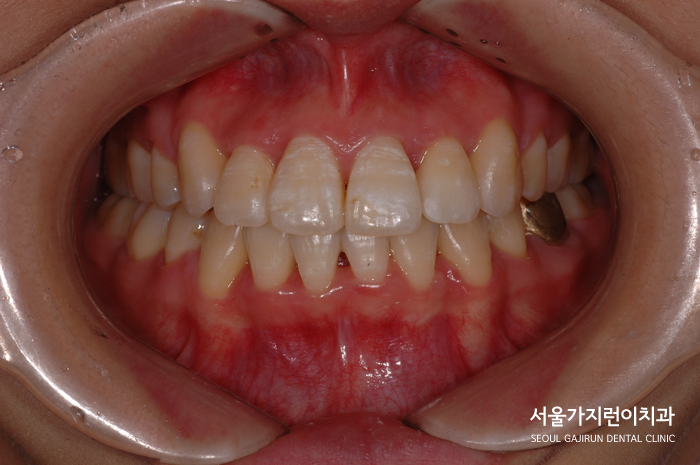

교정이 완료된 이후 모습인데요. 정중선도 맞는 모습을 볼 수 있고 좌우 교합의 균형도 잘 맞아 편측 저작 우려도 해소된 모습을 볼 수 있었어요. 무엇보다 치아의 각도가 제대로 세워지면서 교합선도 자연스러워지고 돌출감도 많이 개선이 되었는데요. 이후 환자분이 집중해줄 부분은 고정식 유지장치를 사용했기 때문에 유지장치 주변으로 치석이 쌓이지 않도록 관리해 주는 것이에요.